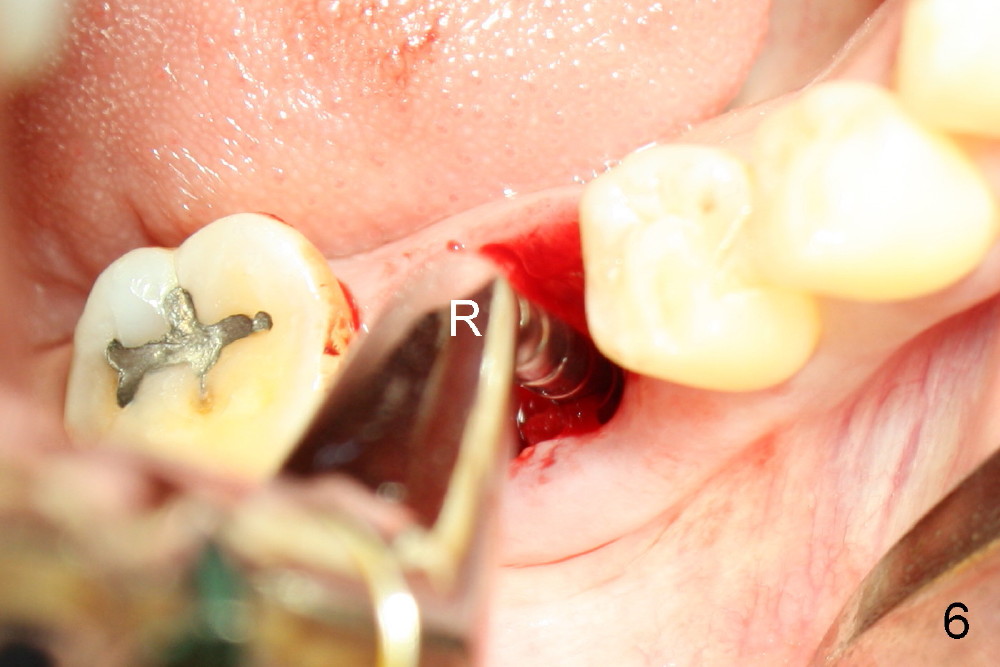

A sixty-year-old lady fractured the crown of the lower right first molar (Fig.1). The residual roots were sectioned (Fig.2 between arrowheads) and removed. The septum (Fig.3 *) is round on the top between mesial and distal sockets (1,2). Thin osteotomes (bone scalpel, bone blade; Fig.4: T) were used to section the septum mesiodistally. Fig.5 shows the sectioned septum, which makes it easy to insert round tapered osteotomes (Fig.5 inset green; Fig.6 R) without slipping either into the mesial or distal socket.